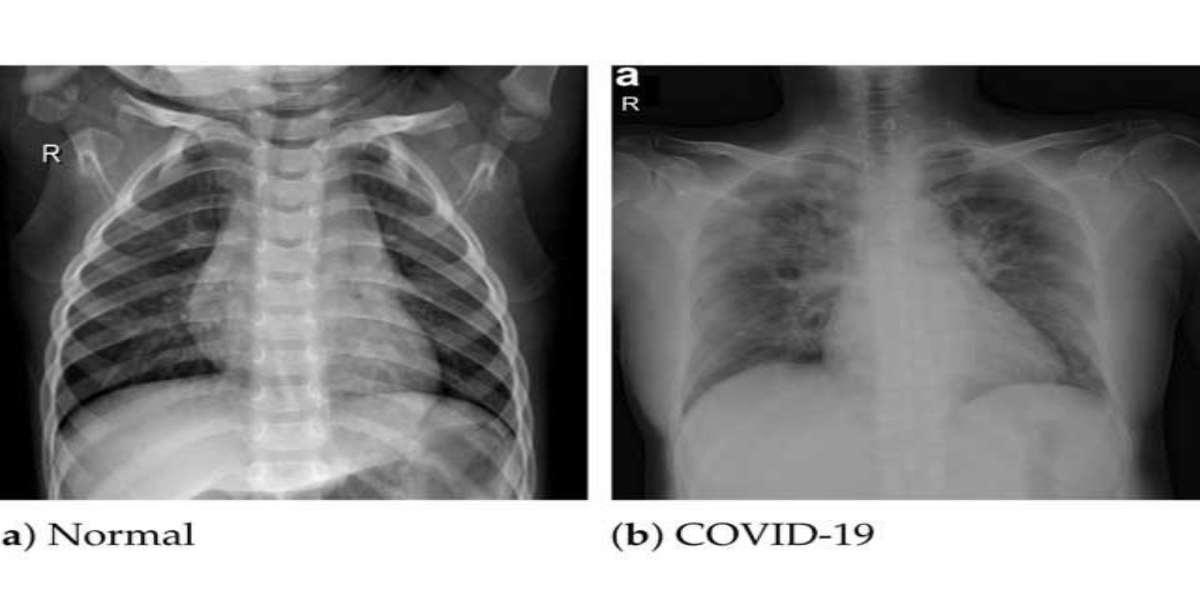

تاہم یونیورسٹی آف ویسٹ اسکاٹ لینڈ کی جانب سے جاری کردہ اعلامیے میں بتایا گیا ہے کہ اس کے ذریعے کورونا سے متاثر اور صحت مند افراد کے پھیپھڑوں کی لی گئیں تین ہزار سے زائد تصاویر کی جانچ کی گئی تھی، جس کے نتائج پی سی آر سے زیادہ بہتر آئے ہیں۔

سائنسی ماہرین کی ٹیم کے مطابق اس ٹیکنالوجی میں سافٹ ویئر اور الگورتھم کو 3000 کے قریب ایکسرے پر تربیت دی گئی ہے۔ ایکسرے کے ڈیٹا میں تندرست انسان، کووڈ 19 مریضوں اور نمونیا کے مریضوں کے ایکسرے شامل کئے گئے تھے۔

سافٹ ویئر نے سینے کے ظاہری ایکسرے کی بنیاد پر مختلف کیفیات کی تربیت حاصل کیں اور یوں اپنے الگورتھم کی بنا پر درست ترین تشخیص کرنے لگا۔